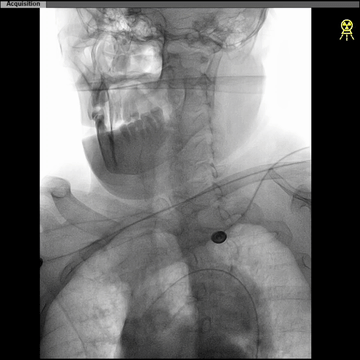

CTA:左ICA起始部重度狭窄,左CCA与无名动脉短共干,左CCA起始段走行明显向左,与主动脉弓呈显著锐角。

5F长椎管(125cm)+6F长鞘(90cm Cook)同轴,椎管头端旋调抵进共干开口,常规泥鳅导丝超选进入左CCA远端,因其近段与弓成角迂曲明显,导丝支撑不足,椎管尝试推进入左CCA失败。

更换125cm 5F预塑型西蒙管,在左锁骨下成形后,成功超选到左CCA。

西蒙管于左CCA造影,用硬泥鳅导丝超选入枕动脉,并西蒙管前推上高到枕动脉,加强上支撑,后长鞘顺利过弓,抵达左CCA远端。

建立治疗通路后,保护伞下(NAV6 4-7mm)行左侧ICA起始部狭窄支架植入(wallstent 9*40mm)。